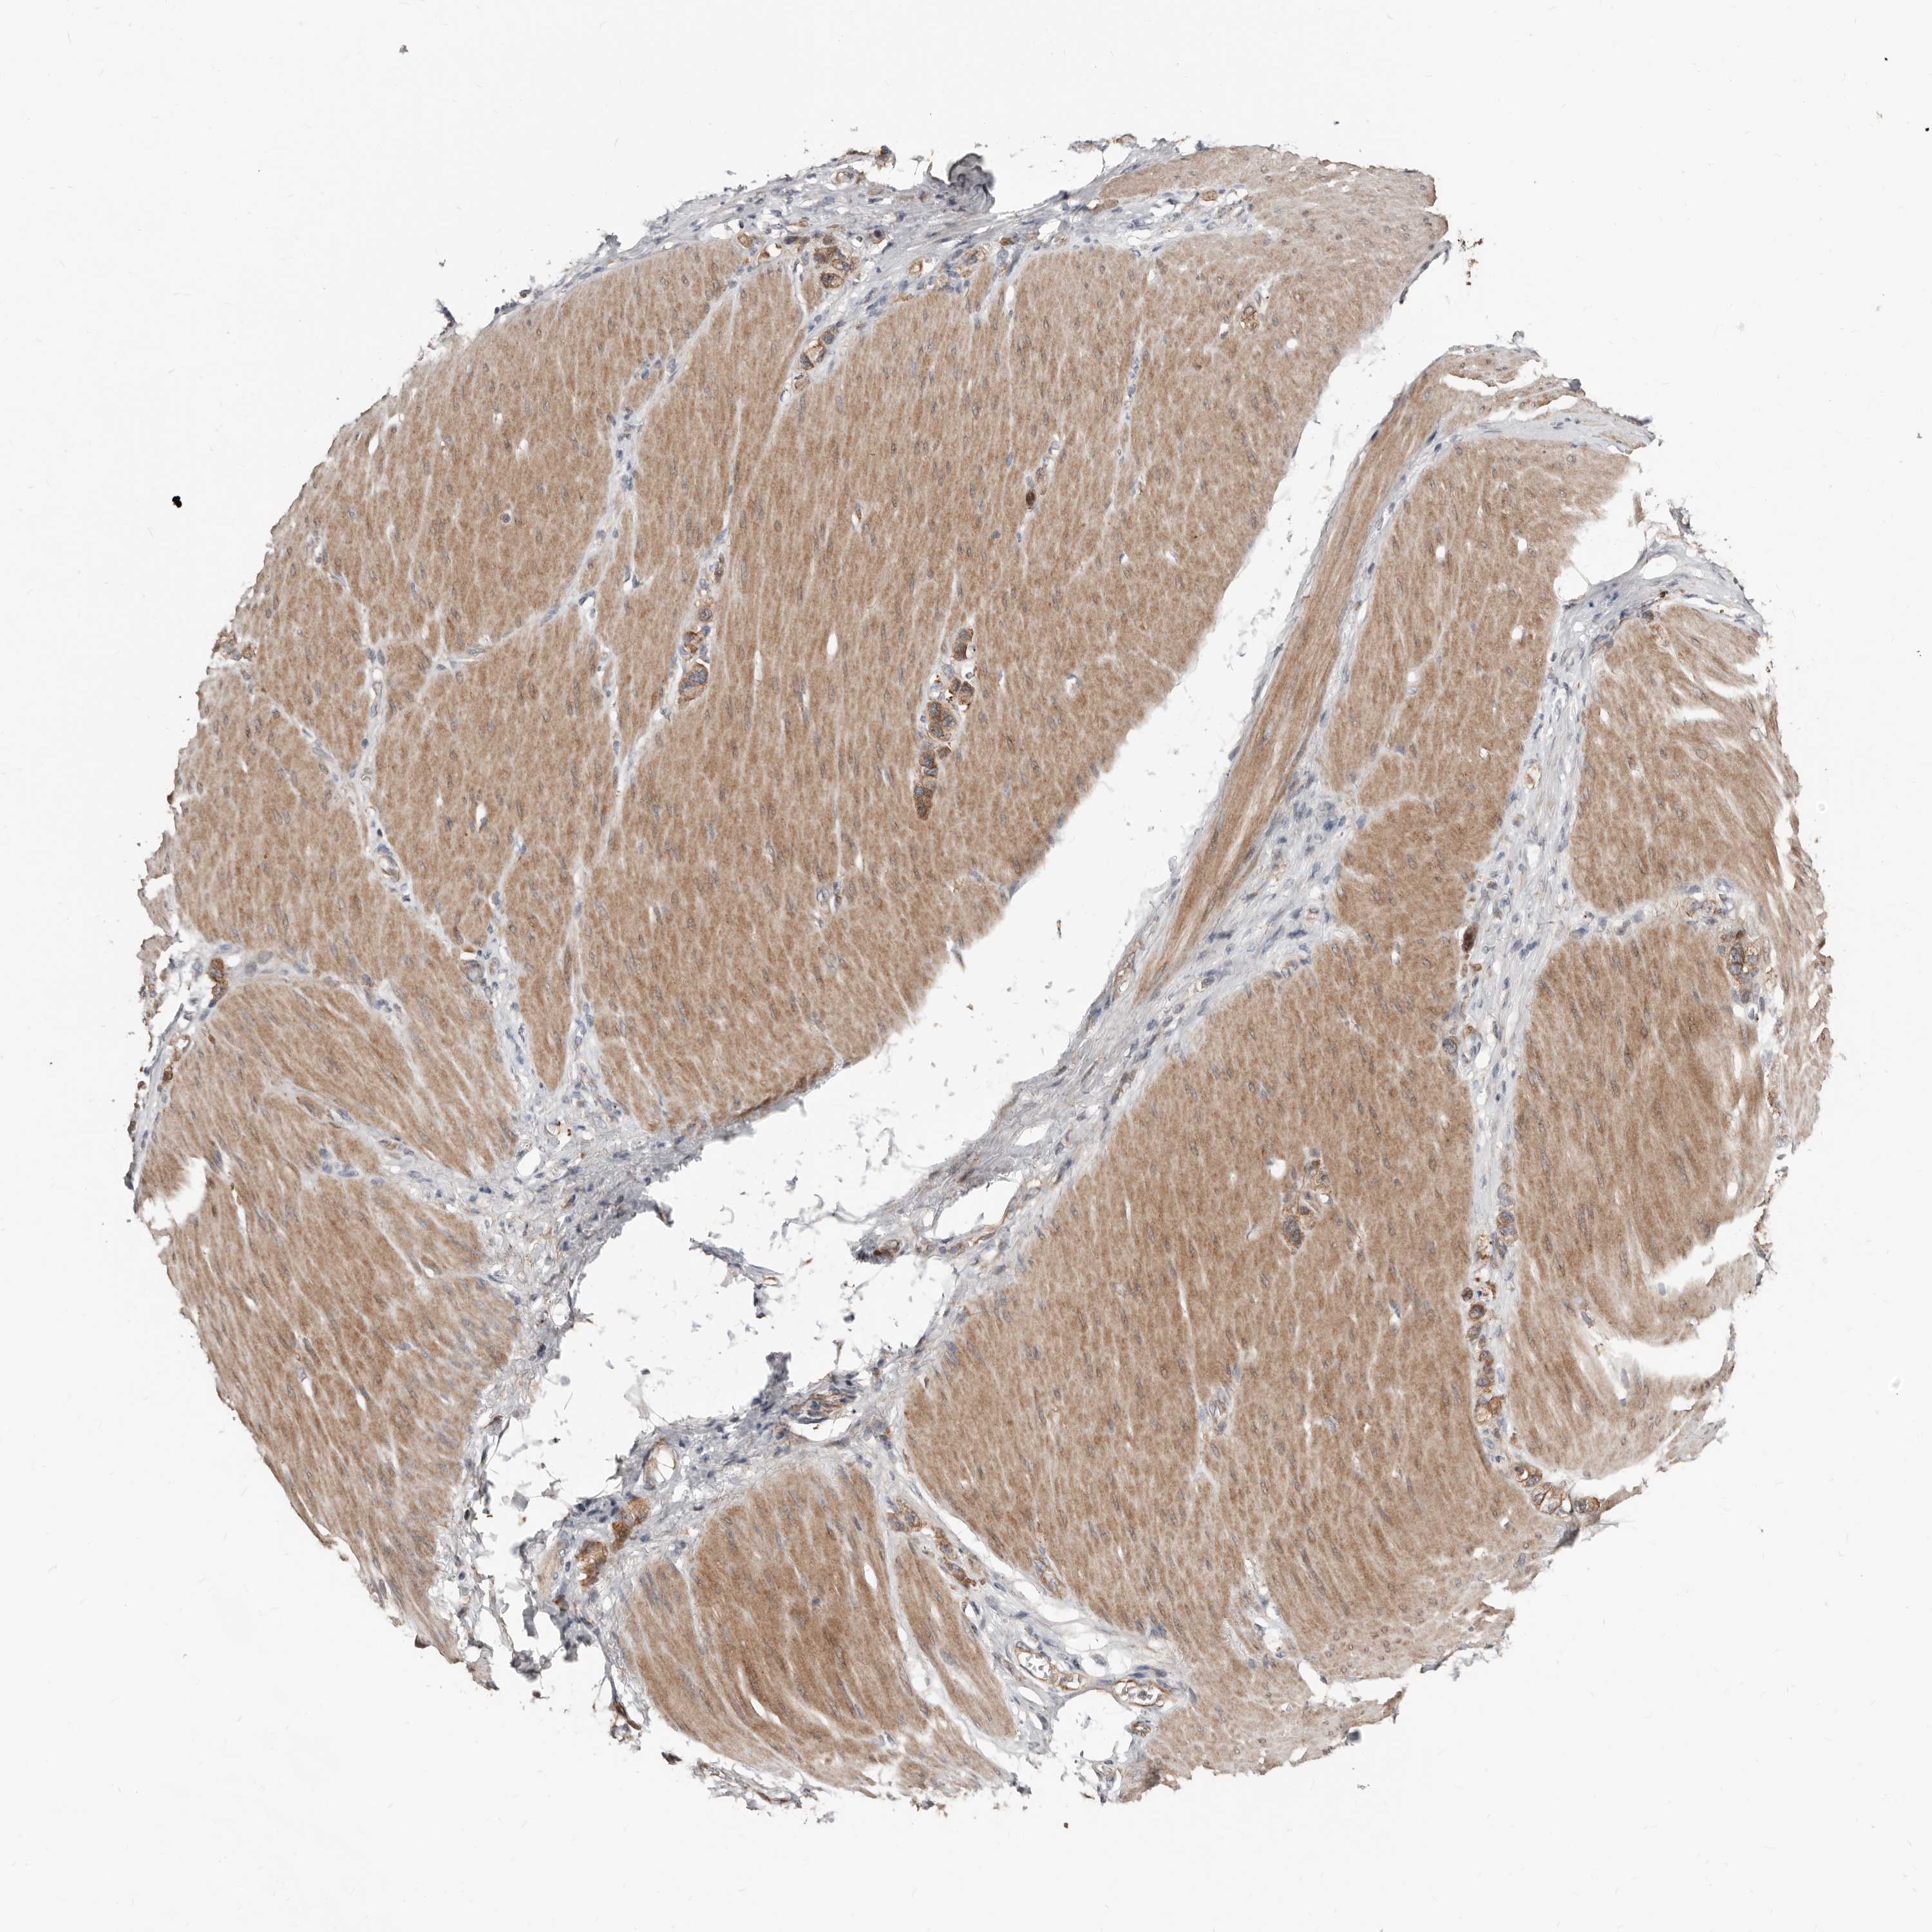

STOMACH CANCER - Protein expressioni

A mouse-over function shows sample information and annotation data. Click on an image to view it in a full screen mode. Samples can be filtered based on level of antibody staining by selecting one or several of the following categories: high, medium, low and not detected. The assay and annotation is described here.

Antibody stainingi

Antibody staining in the annotated cell types in the current human tissue is reported as not detected, low, medium, or high, based on conventional immunohistochemistry profiling in selected tissues. This score is based on the combination of the staining intensity and fraction of stained cells.

Each image is clickable and will lead to virtual microscopy that enables deeper exploration of all samples and also displays staining intensity scores, fraction scores and subcellular localization as well as patient and tissue information for each sample.

Antibody HPA030059

Staining

High

Medium

Low

Not detected

Intensity

Strong

Moderate

Weak

Negative

Quantity

>75%

75%-25%

<25%

None

Location

Nuclear

Cytoplasmic/membranous

Cytoplasmic/membranous,nuclear

Adenocarcinoma, NOS